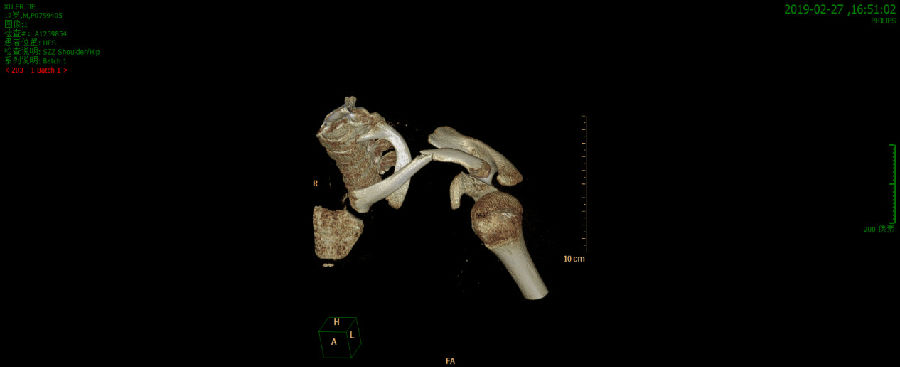

入院后完善左肩关节CT平扫(新)诊断意见:

1、左锁骨中段骨折。

2、左肩胛骨喙突基底部骨折。

请结合临床。

术前左肩关节三维成像